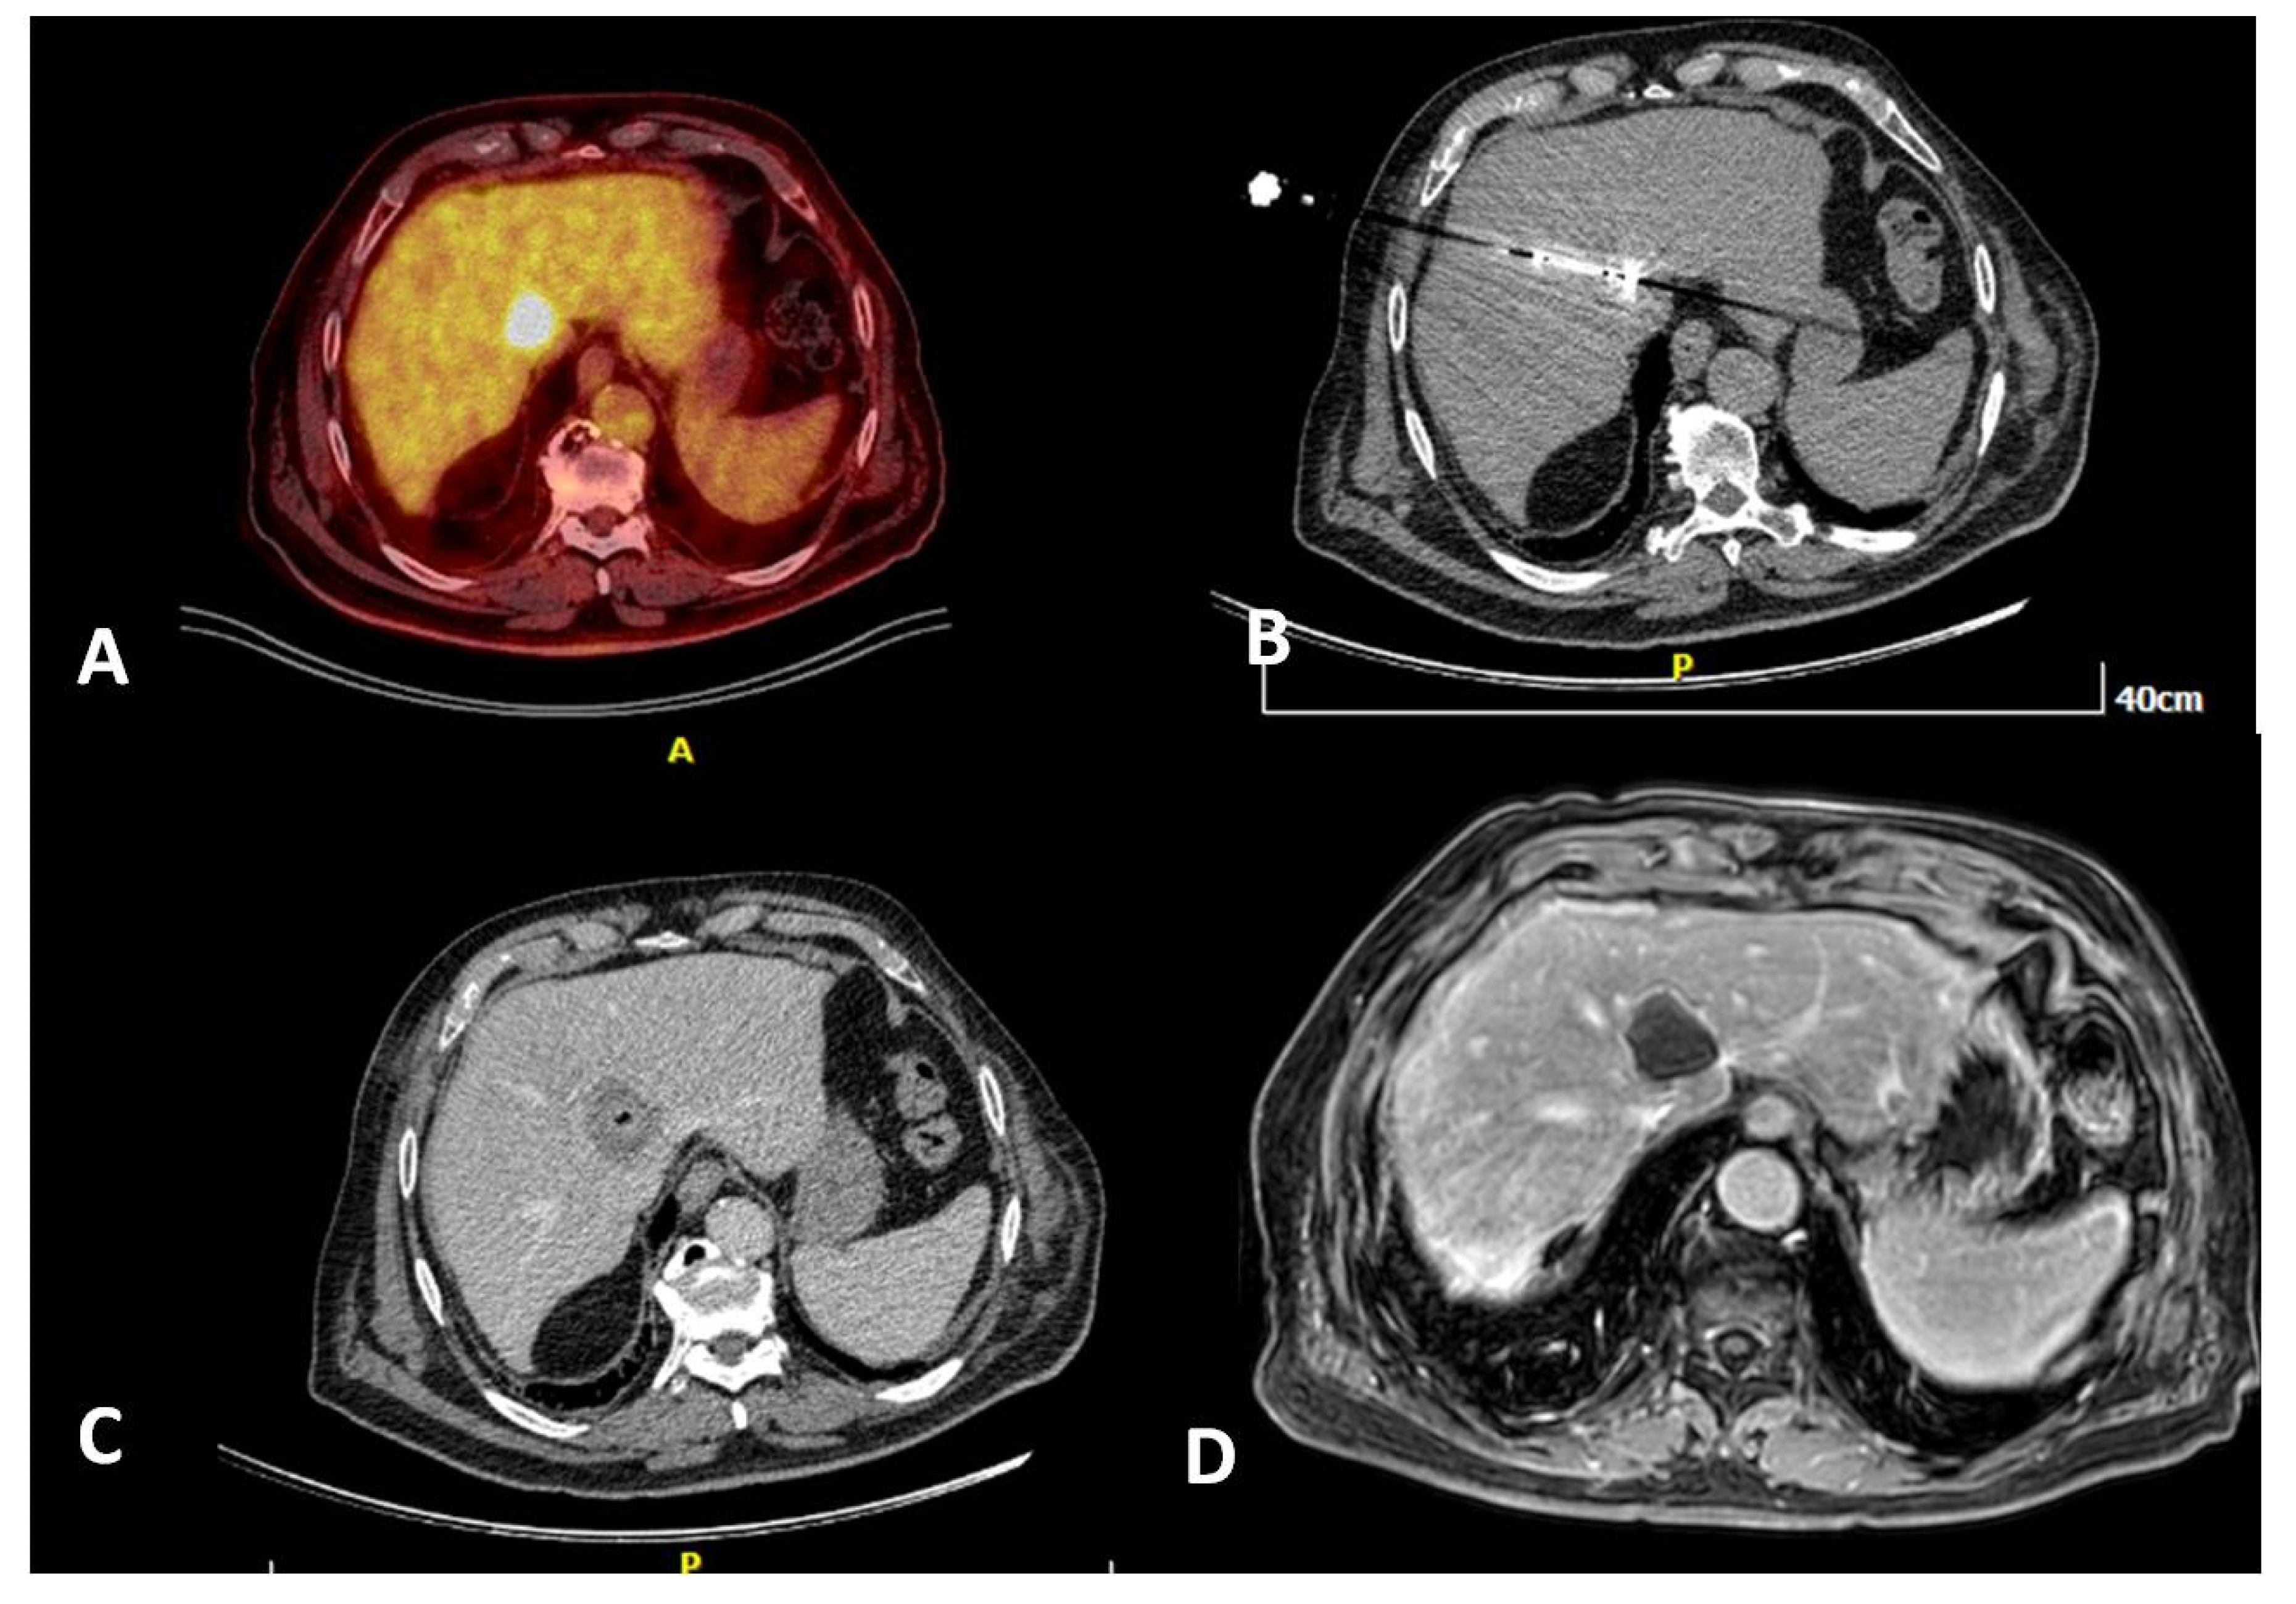

- Cornelis, F.; Sotirchos, V.; Violari, E.; Sofocleous, C.T.; Schoder, H.; Durack, J.C.; Siegelbaum, R.H.; Maybody, M.; Humm, J.; Solomon, S.B. 18F-FDG PET/CT is an immediate imaging biomarker of treatment success after liver metastasis ablation. J. Nucl. Med. 2016, 57, 1052–1057. [Google Scholar] [CrossRef]

- Mauri, G.; Gennaro, N.; De Beni, S.; Ierace, T.; Goldberg, S.N.; Rodari, M.; Solbiati, L.A. Real-time US-(18)FDG-PET/CT image fusion for guidance of thermal ablation of (18)FDG-PET-positive liver metastases: The added value of contrast enhancement. Cardiovasc. Intervent. Radiol. 2019, 42, 60–68. [Google Scholar] [CrossRef]

- Ryan, E.R.; Sofocleous, C.T.; Schöder, H.; Carrasquillo, J.A.; Nehmeh, S.; Larson, S.M.; Thornton, R.; Siegelbaum, R.H.; Erinjeri, J.P.; Solomon, S.B. Split-dose technique for FDG PET/CT-guided percutaneous ablation: A method to facilitate lesion targeting and to provide immediate assessment of treatment effectiveness. Radiology 2013, 268, 288–295. [Google Scholar] [CrossRef]

- Cornelis, F.H.; Petre, E.N.; Vakiani, E.; Klimstra, D.; Durack, J.C.; Gonen, M.; Osborne, J.; Solomon, S.B.; Sofocleous, C.T. Immediate postablation 18F-FDG injection and corresponding SUV are surrogate biomarkers of local tumor progression after thermal ablation of colorectal carcinoma liver metastases. J. Nucl. Med. 2018, 59, 1360–1365. [Google Scholar] [CrossRef]

- Winkelmann, M.T.; Archid, R.; Gohla, G.; Hefferman, G.; Kübler, J.; Weiss, J.; Clasen, S.; Nikolaou, K.; Nadalin, S.; Hoffmann, R. MRI-guided percutaneous thermoablation in combination with hepatic resection as parenchyma-sparing approach in patients with primary and secondary hepatic malignancies: Single center long-term experience. Cancer Imaging 2020, 20, 37. [Google Scholar] [CrossRef]